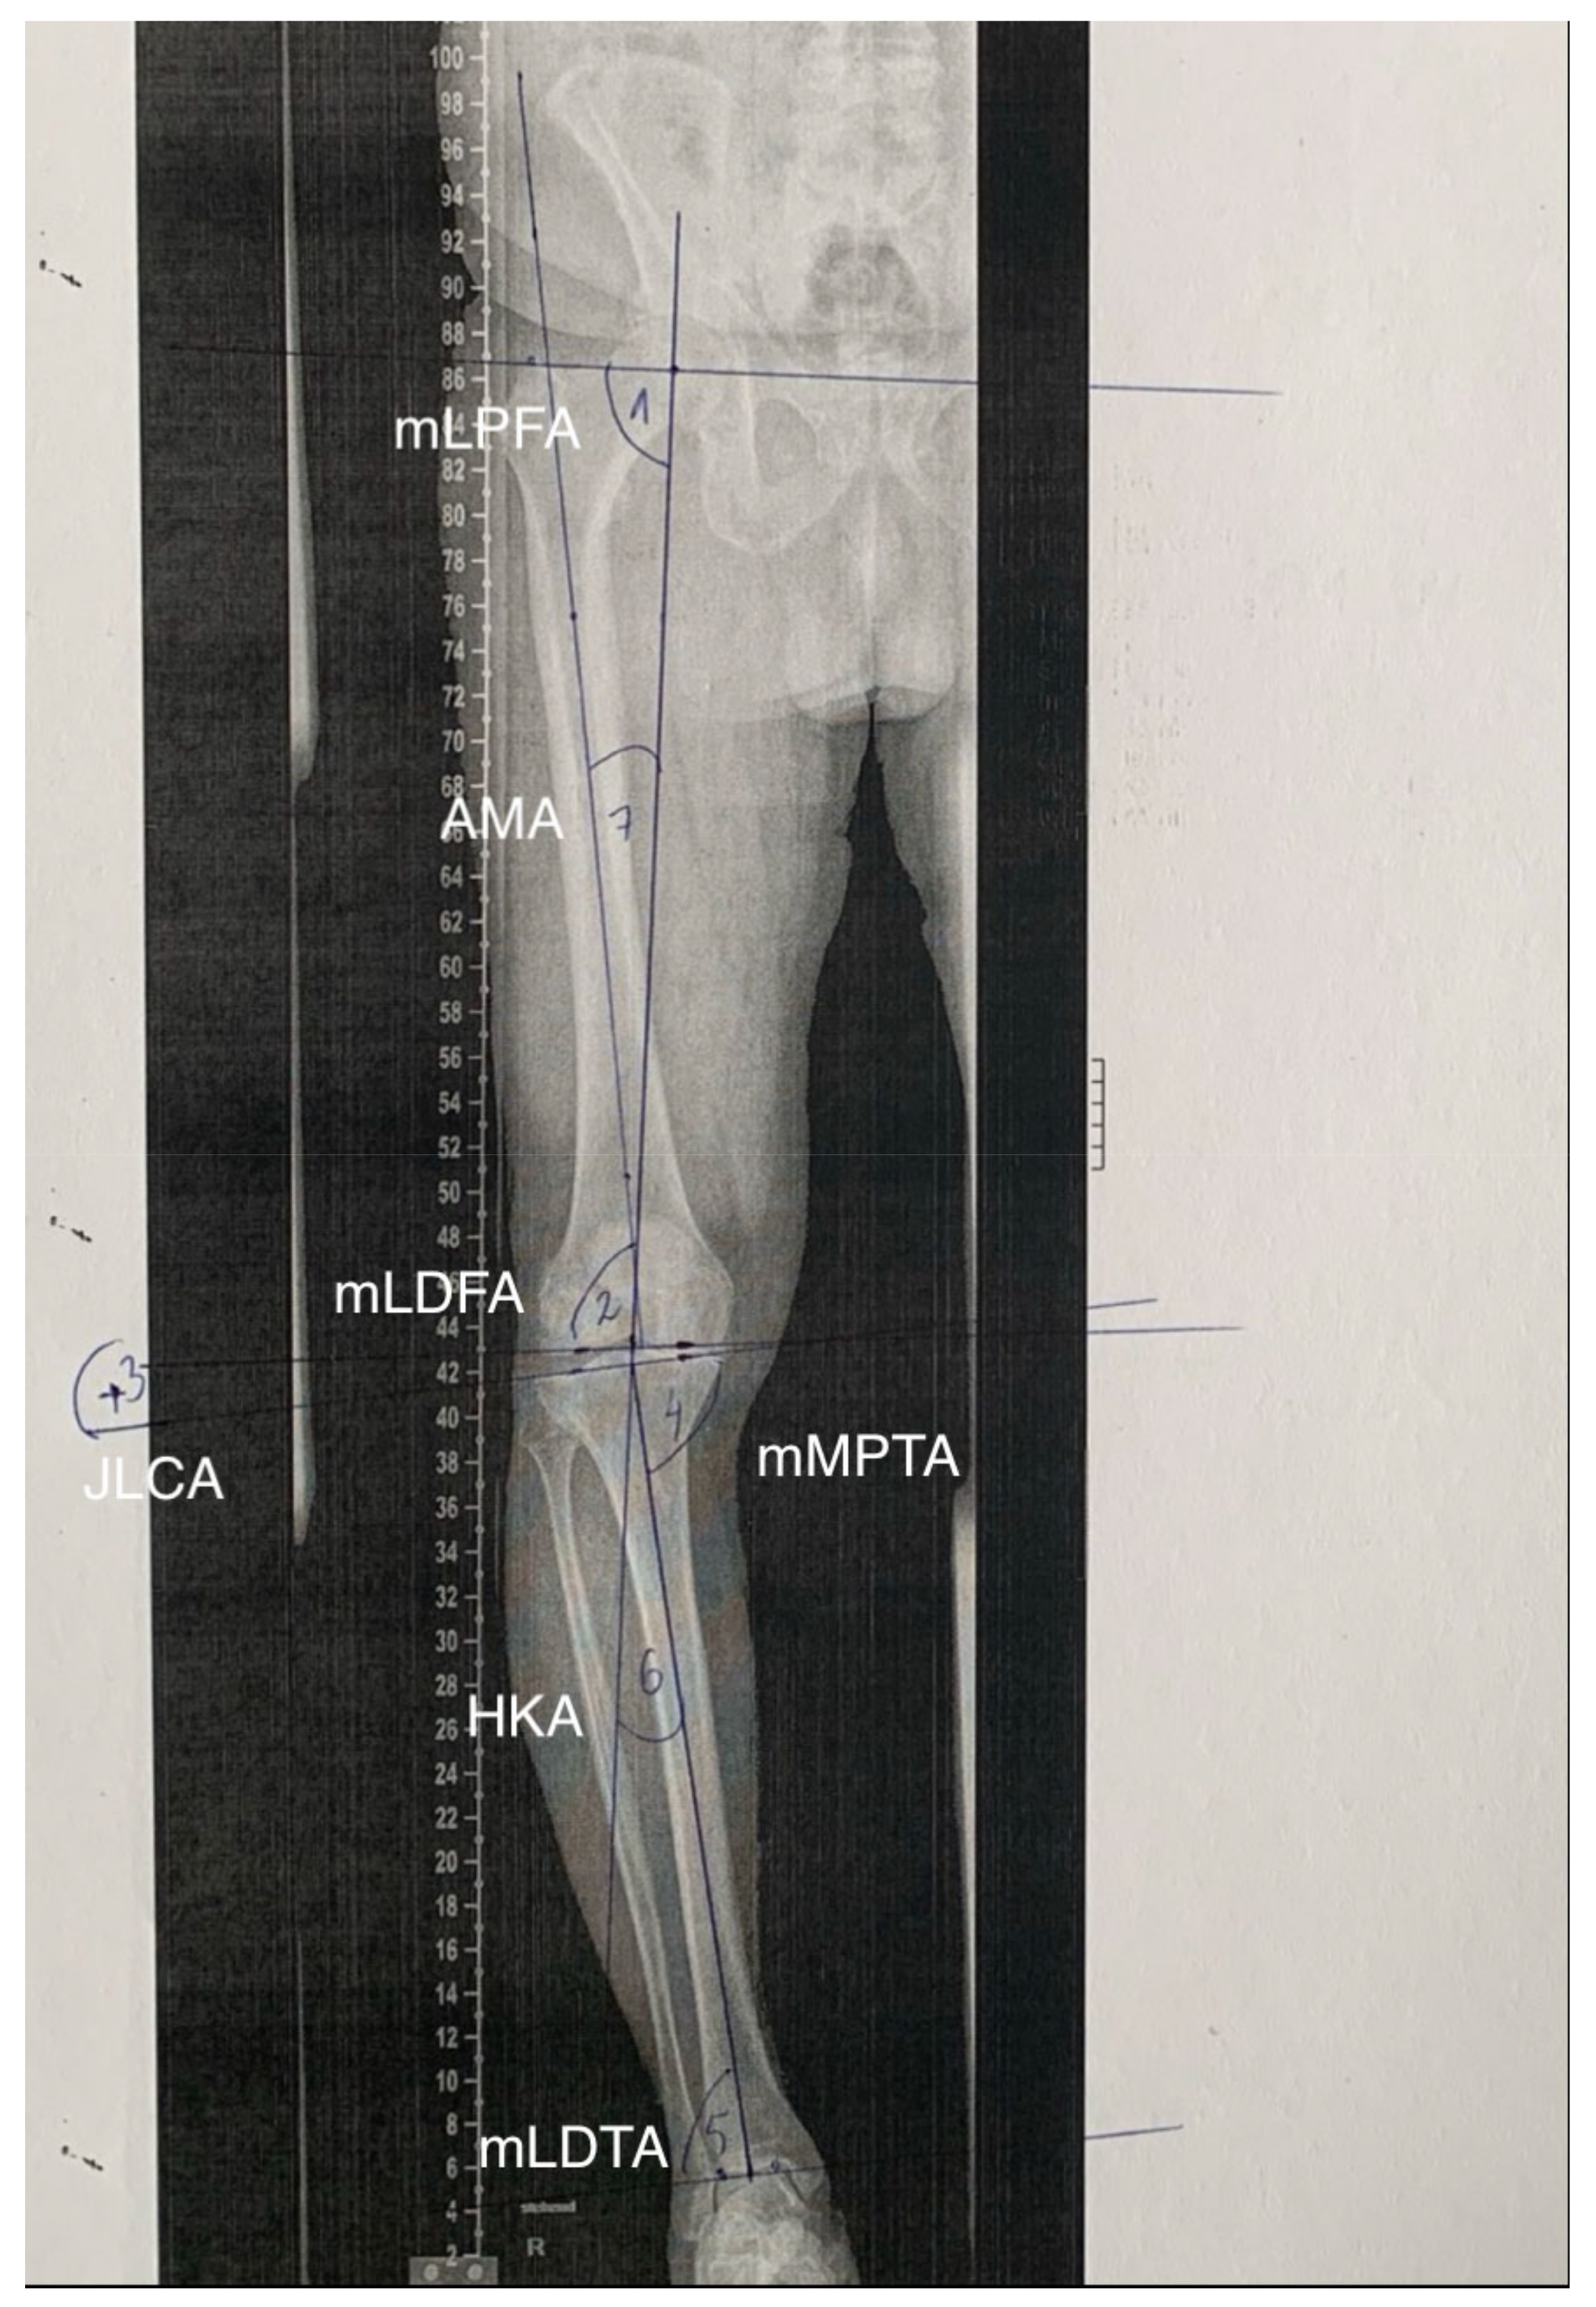

2.2. Software Measurements